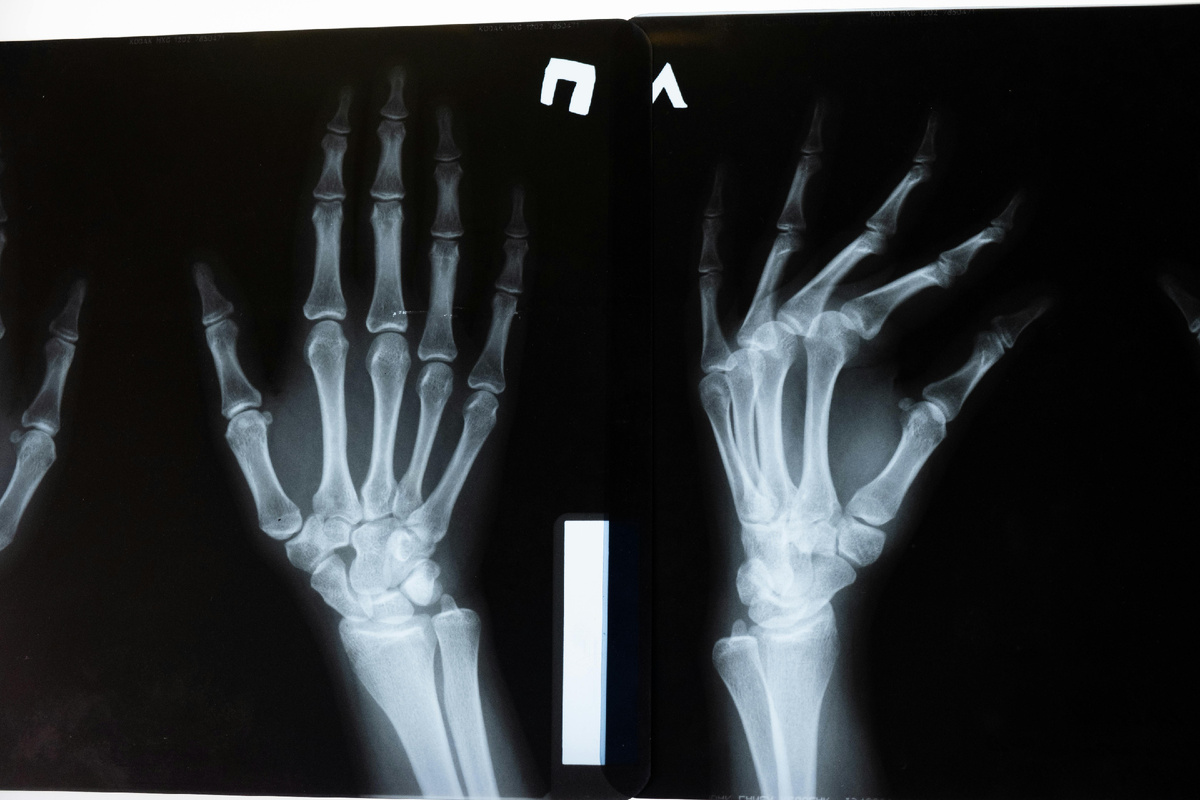

В октябре отмечается всемирный день борьбы с остеопорозом. Это «тихое заболевание», которое может не подавать виду до первого перелома. Хрупкие и ослабленные кости так и норовят сломаться даже при обычном чихании или кашле. Разбираемся, как питание и отказ от вредных привычек (которые, казалось бы, с костями никак не связаны) поможет предотвратить болезнь. В чем проблема?

При остеопорозе кости становятся более слабыми и хрупкими, что увеличивает риск переломов даже при небольшой нагрузке.

Заболевание может прогрессировать без боли и выраженных симптомов до самого перелома. К тому же, получить остеопороз можно в любом возрасте. Факторы риска — менопауза у женщин, активное курение, злоупотребление алкоголем независимо от пола.